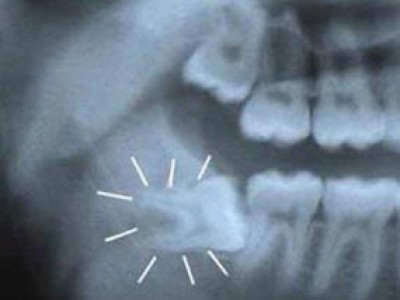

Khi răng khôn gây ra hoặc có xu hướng gây ra tác hại đối với răng, lợi và xương ở xung quanh thì cần nhổ. 1. Sâu răng Do răng khôn

Răng khôn là răng nằm phía trong cùng của hai hàm răng của người trưởng thành. Răng khôn (răng số tám hay răng hàm lớn thứ ba) là răng mọc cuối